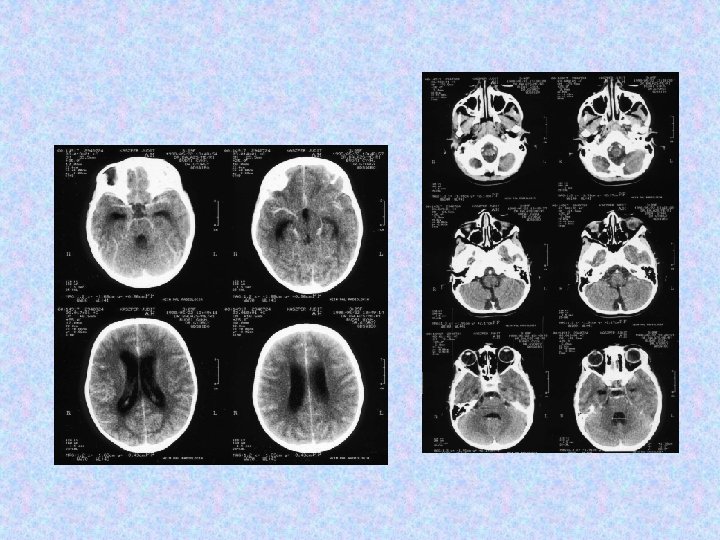

Esetismertetés K. J. • 1997. 04. született lány , 3. gyermek, normális perinatális fejlődés, terhelő szülői és autoanamnézis nélkül. • 1998. márciusában hyperpyrexiával, hányingerrel, hányással járó állapot miatt kezelték, dg. : napszúrás. • 1998. május elején fejfájás, gyakori hányás miatt indult kivizsgálása. • Az elkészült CT vizsgálat hydrocephalust igazolt, ICF jelei mellett.

• MR vizsgálat készült liquorpassage zavar miatt. • MR vizsgálat meningeális kontraszthalmozást mutatott a bazális ciszterna, a cerebri media, a ciszterna magna területében. • Felmerült a meningitis basilaris gyanúja, amely nem igazolódott. • Liquor fehérje: 7, 05 g/l, glükóz: 5, 0 mmol/l, sejtszám 10/látótér. Baktérium nem tenyészett ki. Mikrobiológia, szerológia negatív. Citológia gyulladásos szedimentációt véleményezett. Tumor sejtek nem voltak láthatóak. • Spinalis MR thoracalis compressziót, meningeális szóródást mutatott.

• 1998. május 25. és 1998. június 25. között a beteget a Szent László Kórházban kezelték. Minden reggel hányt az ozmotikus terápia (mannitol) ellenére, csak acetazolamidra reagált. Azóta gyakorlatilag tünetmentes, hányásai, dührohamai megszűntek; agresszióját és konfúzióját korábban a liquor nyomás fluktuáci. A fent említett gyógyszerek dózisának csökkentésekor a tünetek visszatértek. • 1998. június 19 -én készült MRI a halmozó részek progresszióját mutatta. A hydrocephalus jeleinek és a klinikai kép progressziója miatt a beteg az OITI-ba került át.

• 1998. június 30 -án jobb oldali VP shunt került behelyezésre. Biopsziát későbbre terveztek. • 1998. július 20 -án készült CT beszűkült szupratentoriális kamrarendszert mutat. A shunt jó pozícióban helyezkedik el. • Az 1998. augusztusi MRI nem mutat progressziót sem a kraniális, sem a spinális folyamatokban. • Az 1998. december 7 -i MR felvétel progressziót mutat. Neurológiailag a betegnek kétoldali Babinski tünetei, élénk mélyízületi reflexei vannak, izomzata hypotoniás. Egyebekben negatív státusz. A shunt közepes nyomás mellett jól vezet.